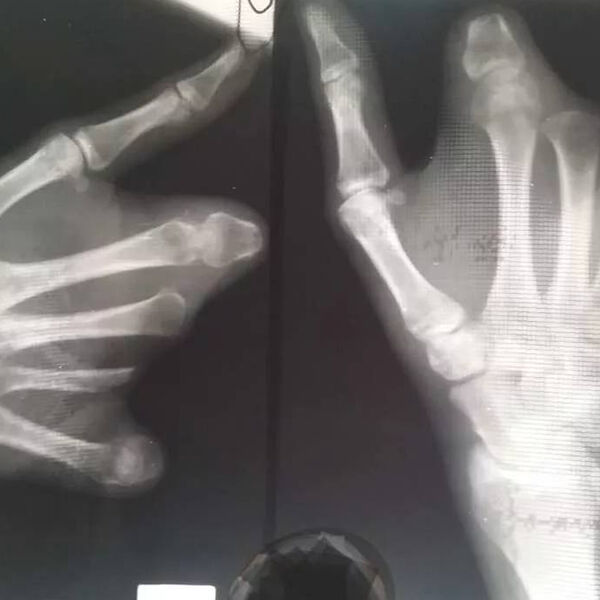

«Несовершеннолетний поступил в больницу с пиротехнической травмой, контузией левого глаза, ссадинами лица и раной левой кисти», — рассказали полицейские.